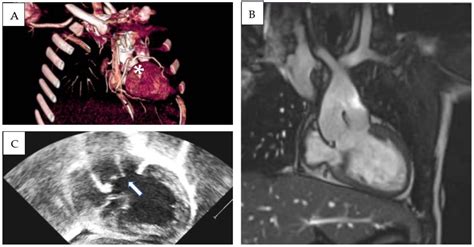

Cardiac Magnetic Resonance Imaging (CMR)

Cardiac Magnetic Resonance Imaging (CMR) is a non-invasive imaging technique that uses magnetic fields and radio waves to produce detailed images of the heart. CMR provides high-resolution images of the heart's structure and function, making it a valuable tool for evaluating the Left Ventricle Outlet. CMR can assess the aortic valve's structure and function, visualize any obstructions in the Left Ventricle Outlet, and measure the pressure gradient across the outlet. It can also evaluate the left ventricle's size, shape, and function, providing a comprehensive assessment of cardiac health.

CMR is particularly useful for evaluating complex cardiac anatomy and assessing the extent of myocardial fibrosis, which can be associated with various cardiovascular conditions. However, CMR may not be suitable for all patients, particularly those with implanted devices or severe claustrophobia.